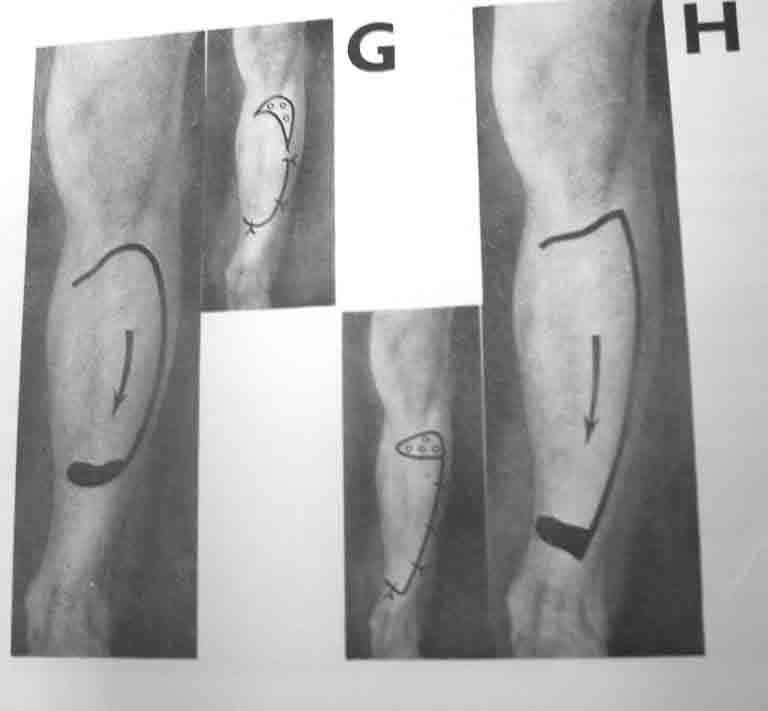

Глубокоуважаемый Павел Анатольевич! БОльшое спасибо за исчерпывающие комментарии! С Капланом, согласен, погорячился. Как Вы считаете, возможна ли в этой ситуации пластика перемещенным кожным лоскутом на широком основании (например, как на прилагаемом фото)?

Данный лоскут не имеет осевого кровоснабжения. Операция по его выделению травматичная. У пациента 60 лет очень высокий риск некроза этого лоскута после его отслойки. А если даже 50% площади этого лоскута некротизируется, то мы получим рану, во много раз большую, чем исходная. Я бы не стал его использовать.

“возможна ли в этой ситуации пластика перемещенным кожным лоскутом на широком основании (например, как на прилагаемом фото)?”

При отсутствии альтернативы закрытия дефекта специалистом, тогда кожным лоскутом на широком основании "cross leg flap". Рекомендую подготовку донорского участока заранее, на задней поверхности голени, срез кожи с подкожной клетчаткой, как на вашем рисунке, приподнимается лоскут от фасции, после гемостаза кожа зашивается заново.

Таким образом подготовленный участок хорошо приживается засчет образования краевого кровообращения, особенно у пожилых и у больных с заболеваниями периферических сосудов. Через 10-12 дней лоскут повторно выделяется по заживающей линии и закрывается дефект, а на донорский участок кожная пластика.